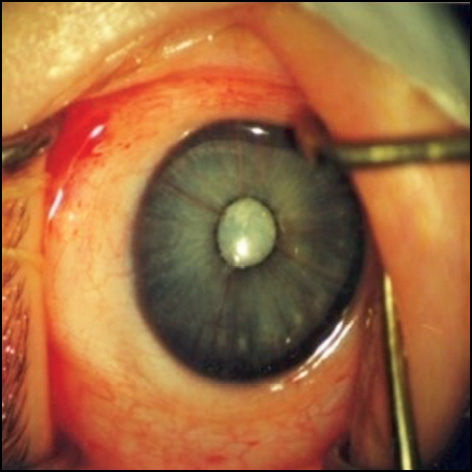

Biomicroscopic examination revealed no changes in the condition of the posterior chamber of the eye and its angle, iris, and ciliary processes. The following forms of CCs were distinguished: full forms on 5 eyes, posterior capsular on 24 eyes, and semi-detached in 3 eyes (Fig. 2).

Fig. 2. The posterior capsule shape of the congenital cataract. Hyaloid arteriosum extending from the posterior capsule to the optic nerve.